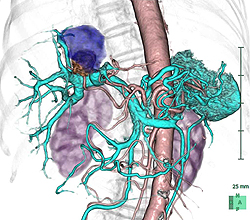

肝細胞癌と肝内胆管癌の混合症例を提示します。図1では、青矢印のやや黒く写るところが肝内胆管癌で、赤矢印の白く写るところが肝細胞癌です。造影剤注入後に早いタイミングで撮影することによって腫瘍の鑑別がしやすくなります。図2は同じ症例の3D画像です。血管構築像を3D作成することによって腫瘍と血管の位置が明確になり、手術の際に役に立ちます。図3は膵臓に沿って断面の傾きを調整した画像(多方向断面)で、膵臓中央部に腫瘍(小矢印に囲まれた部位)があり、腫瘍によって閉塞した膵管(大矢印)が拡張している様子が観察されます。